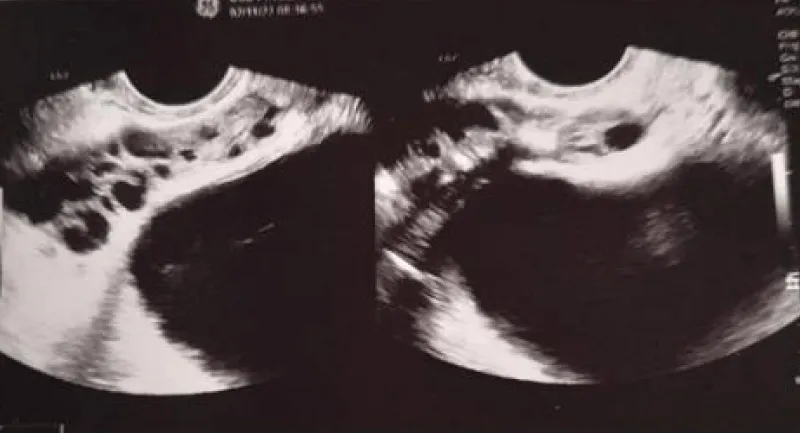

Download Image

Table 1: From doi:10.1038/aja.2012.49.

Figure 5: From doi:10.1038/aja.2012.49.

Dohle, et al. [10] reported that in patients with a history of MAGI, 10% had abnormalities found on transrectal ultrasound of the prostate, such as oedema, dilatation of the seminal vesicles and ejaculatory ducts, intraprostatic calcifications and dilatation of the periprostatic venous plexus”.

Through the transrectal ultrasound of the prostate, it is possible to see oedema, dilatation of the seminal vesicles and ejaculatory ducts, and intraprostatic calcifications.

Imaging (transrectal ultrasound) can show seminal vesicle enlargement.